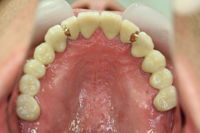

5. 重度歯周炎

歯周ポケットの深さが6mm以上、歯の揺れる幅が2~3mmの歯周炎を重度歯周炎といいます。歯を支える骨は3分の2程度失われて、歯はぐらぐらして硬いものを噛むことができなくなります。

外科的な処置を中心に場合によっては抜歯という選択肢も視野に入れて治療をしてまいります。

重度歯周炎の治療例

重度の歯周炎により上顎の歯が全て外向きにひらき歯間が開いた状態で来院されました。

治療:下顎臼歯部(下奥歯)を抜歯した状態のままになっておりましたので、前歯が強くあたり、歯周病も重なり前歯が開いてしまっていました。下奥歯欠損部はインプラントによる治療、また開いてしまった上顎は矯正により元の位置に戻しました。下に入れたインプラントにより全ての歯が均一に噛み合うようになり、歯周病の治療もスムーズに行えました。

| 期間 | 1年 |

| 費用 | 約200万円 |